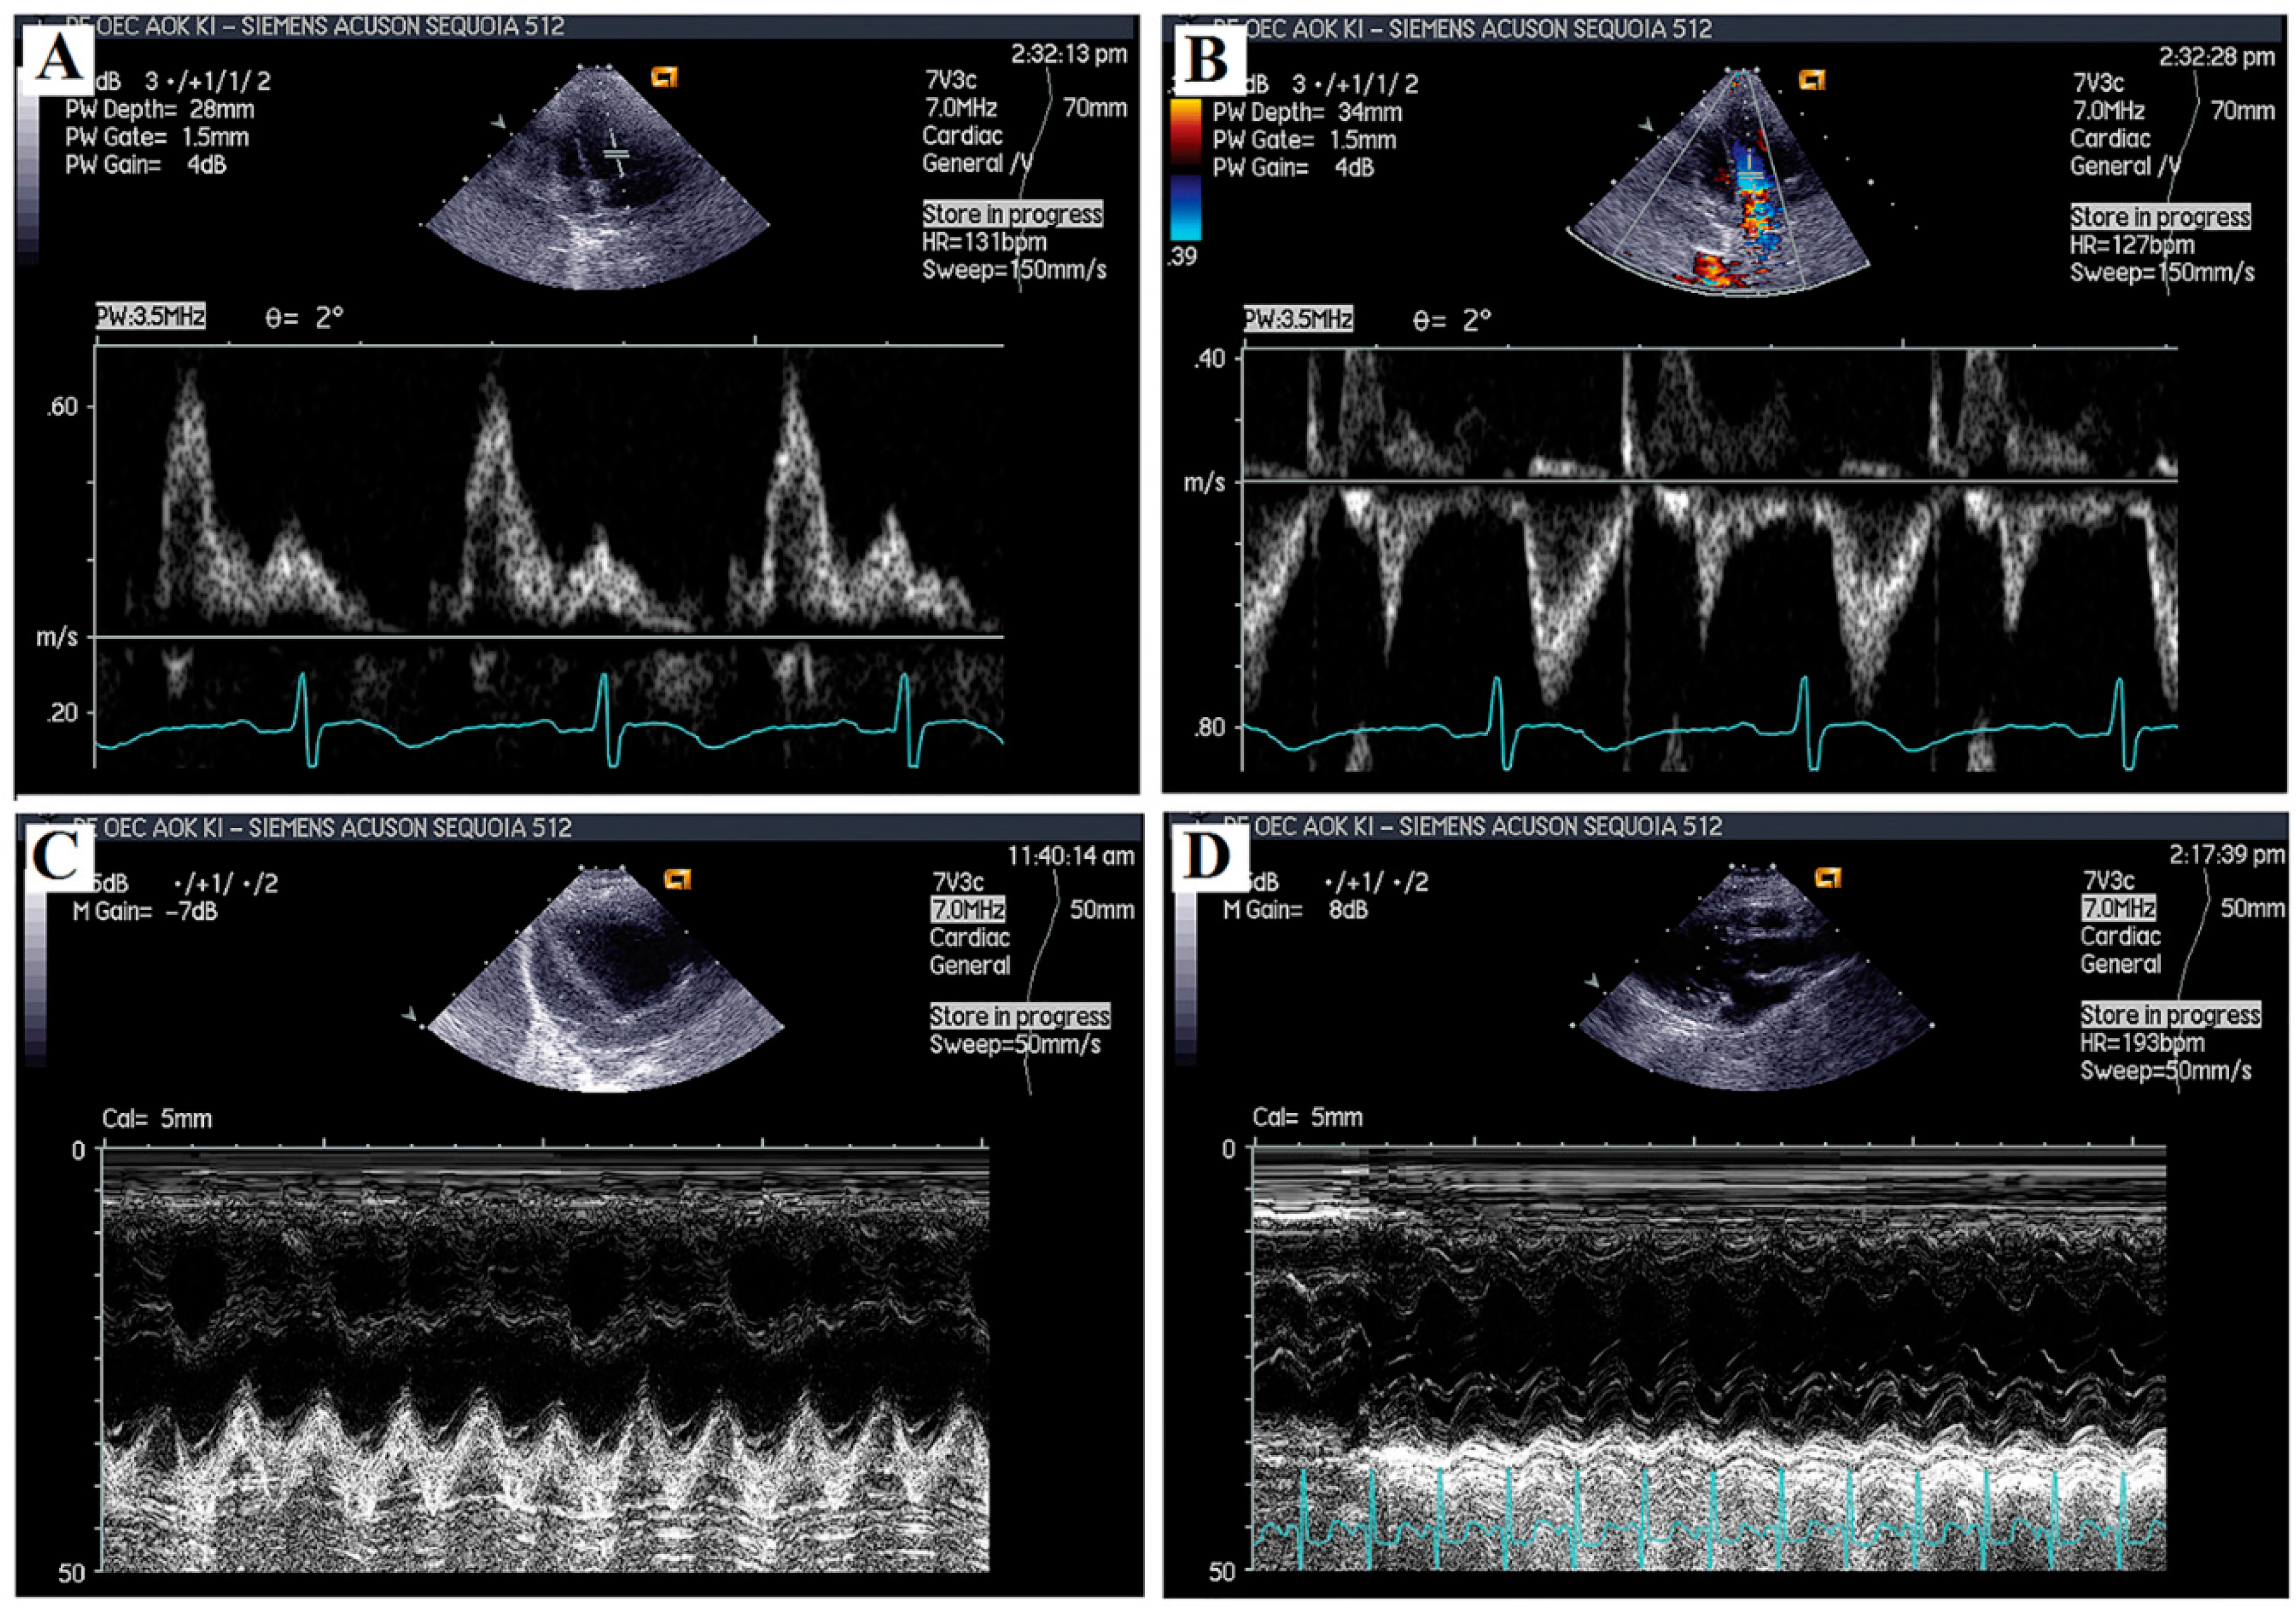

2.2. Echocardiographic Analyses

4.3. Echocardiography